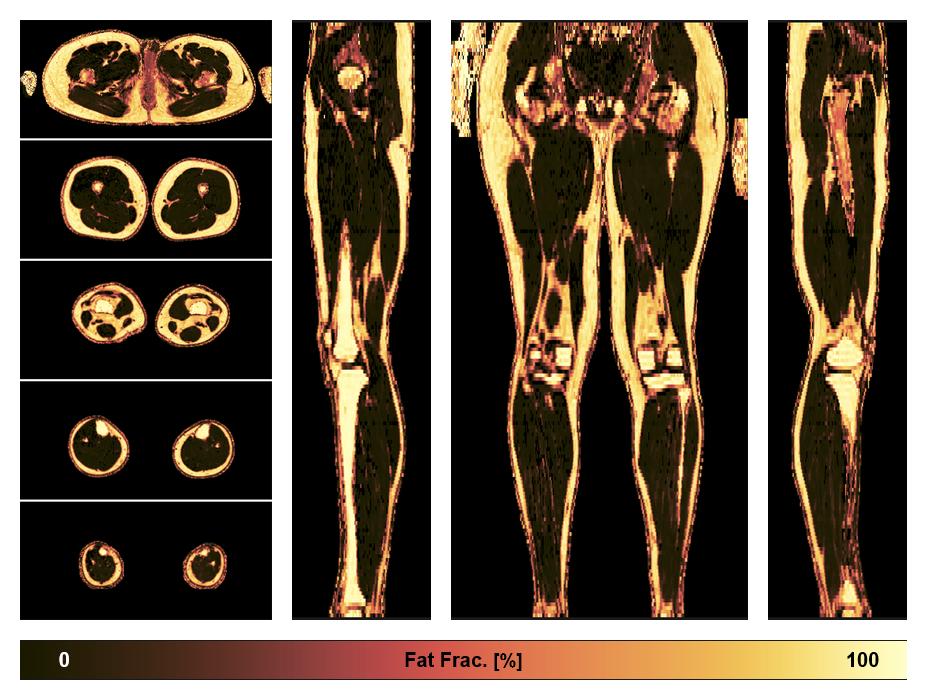

• Fat fraction

The fat fraction of the lower extremity obtained from the dixon reconstruction for muscle water fat quantification.